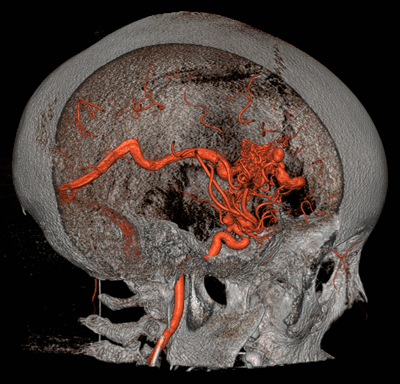

Brain Arteriovenous Malformations (AVMs)

Brain (or cerebral) AVMs are found in about five to twenty percent of people with HHT and can also be successfully treated in most cases. They can be life-threatening or disabling if they bleed. Since they often do not cause warning symptoms prior to bleeding, we recommend screening for them in all people with HHT, even infants. Other types of brain vascular malformations, such as capillary telangiectasias, cavernous malformations, and venous malformations, may be seen in HHT patients. It is not clear if these malformations are seen any more commonly in HHT patients than in patients without HHT, but they are less risky than AVMs and often do not require treatment. Learn more (pdf)

Brain Arteriovenous Malformations (AVMs).